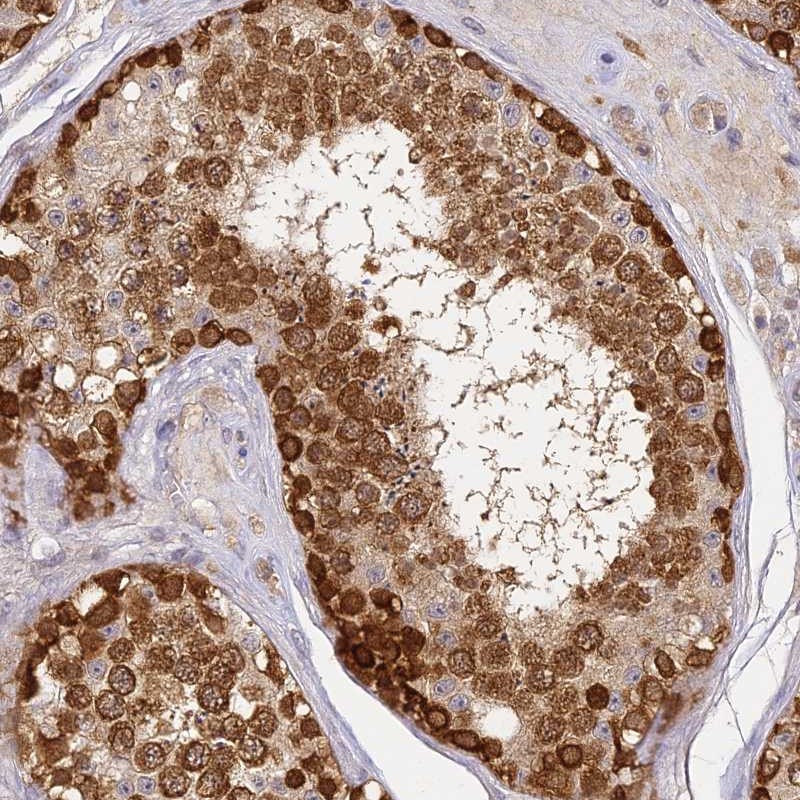

Immunohistochemical staining of human testis shows strong cytoplasmic positivity in cells in seminiferus ducts.